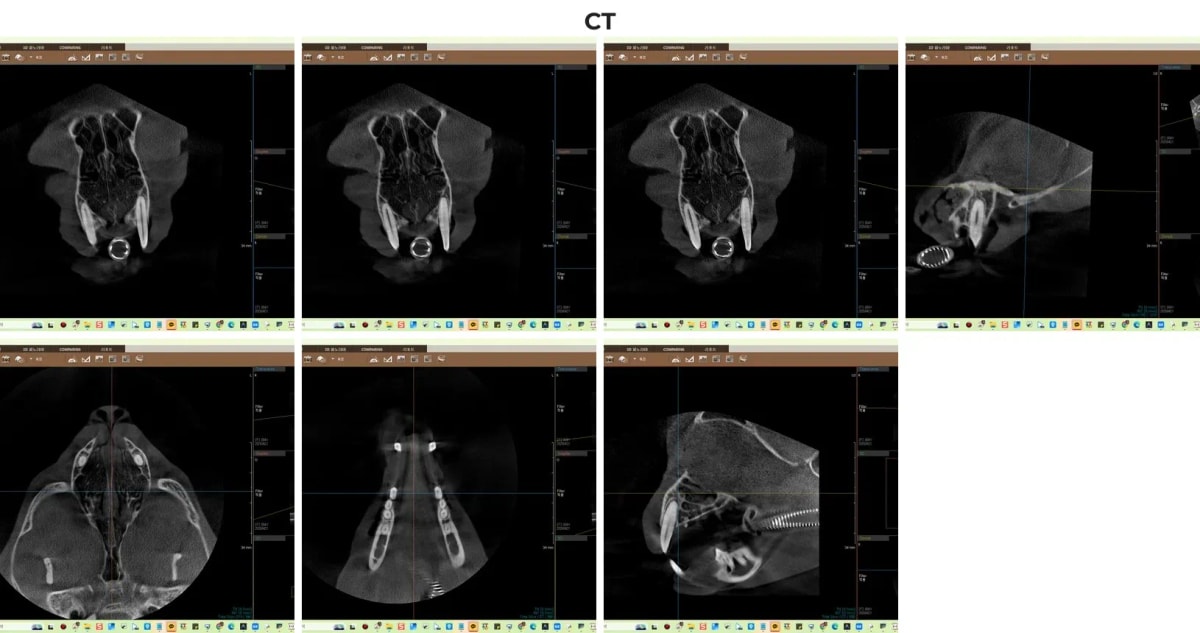

치아가 부러졌을 때 육안으로는 뿌리 내부의 염증이나 미세한 턱뼈 골절을 파악할 수 없습니다. 광주 전남 유일 치과 CT를 활용하면 치아 신경관의 손상 정도와 뿌리 끝 농양 형성 여부를 3D 입체 영상으로 정확히 진단하여, 무분별한 발치를 막고 치아를 살릴 수 있는 결정적인 단서를 제공합니다.

고양이 치과 전용 CT 촬영 결과

CT 촬영 후 곧바로 치과 전용 디지털 엑스레이를 통해 모카의 전체 구강 상태를 확인했습니다. 문제가 된 좌측 상악 송곳니(204번)는 치수(신경)가 노출된 복합 치관 파절(CCF) 상태였으며, 육안으로 잇몸 부종이 확인되었습니다. 하지만 정밀 영상 확인 결과, 다행히 치근단농양(뿌리 끝 염증)이나 치조골 흡수(잇몸뼈가 녹는 현상)는 관찰되지 않았습니다. 즉, 늦지 않게 내원해주신 덕분에 치아를 뽑지 않고 살릴 수 있는 골든타임 안에 진입한 것입니다.

수술 전 고양이 구강 엑스레이 소견